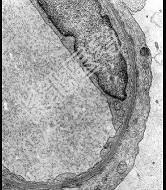

- 单项选择题肾病理光镜及免疫荧光正常,观察电镜下改变, 其病理诊断 ( )

E、微小病变